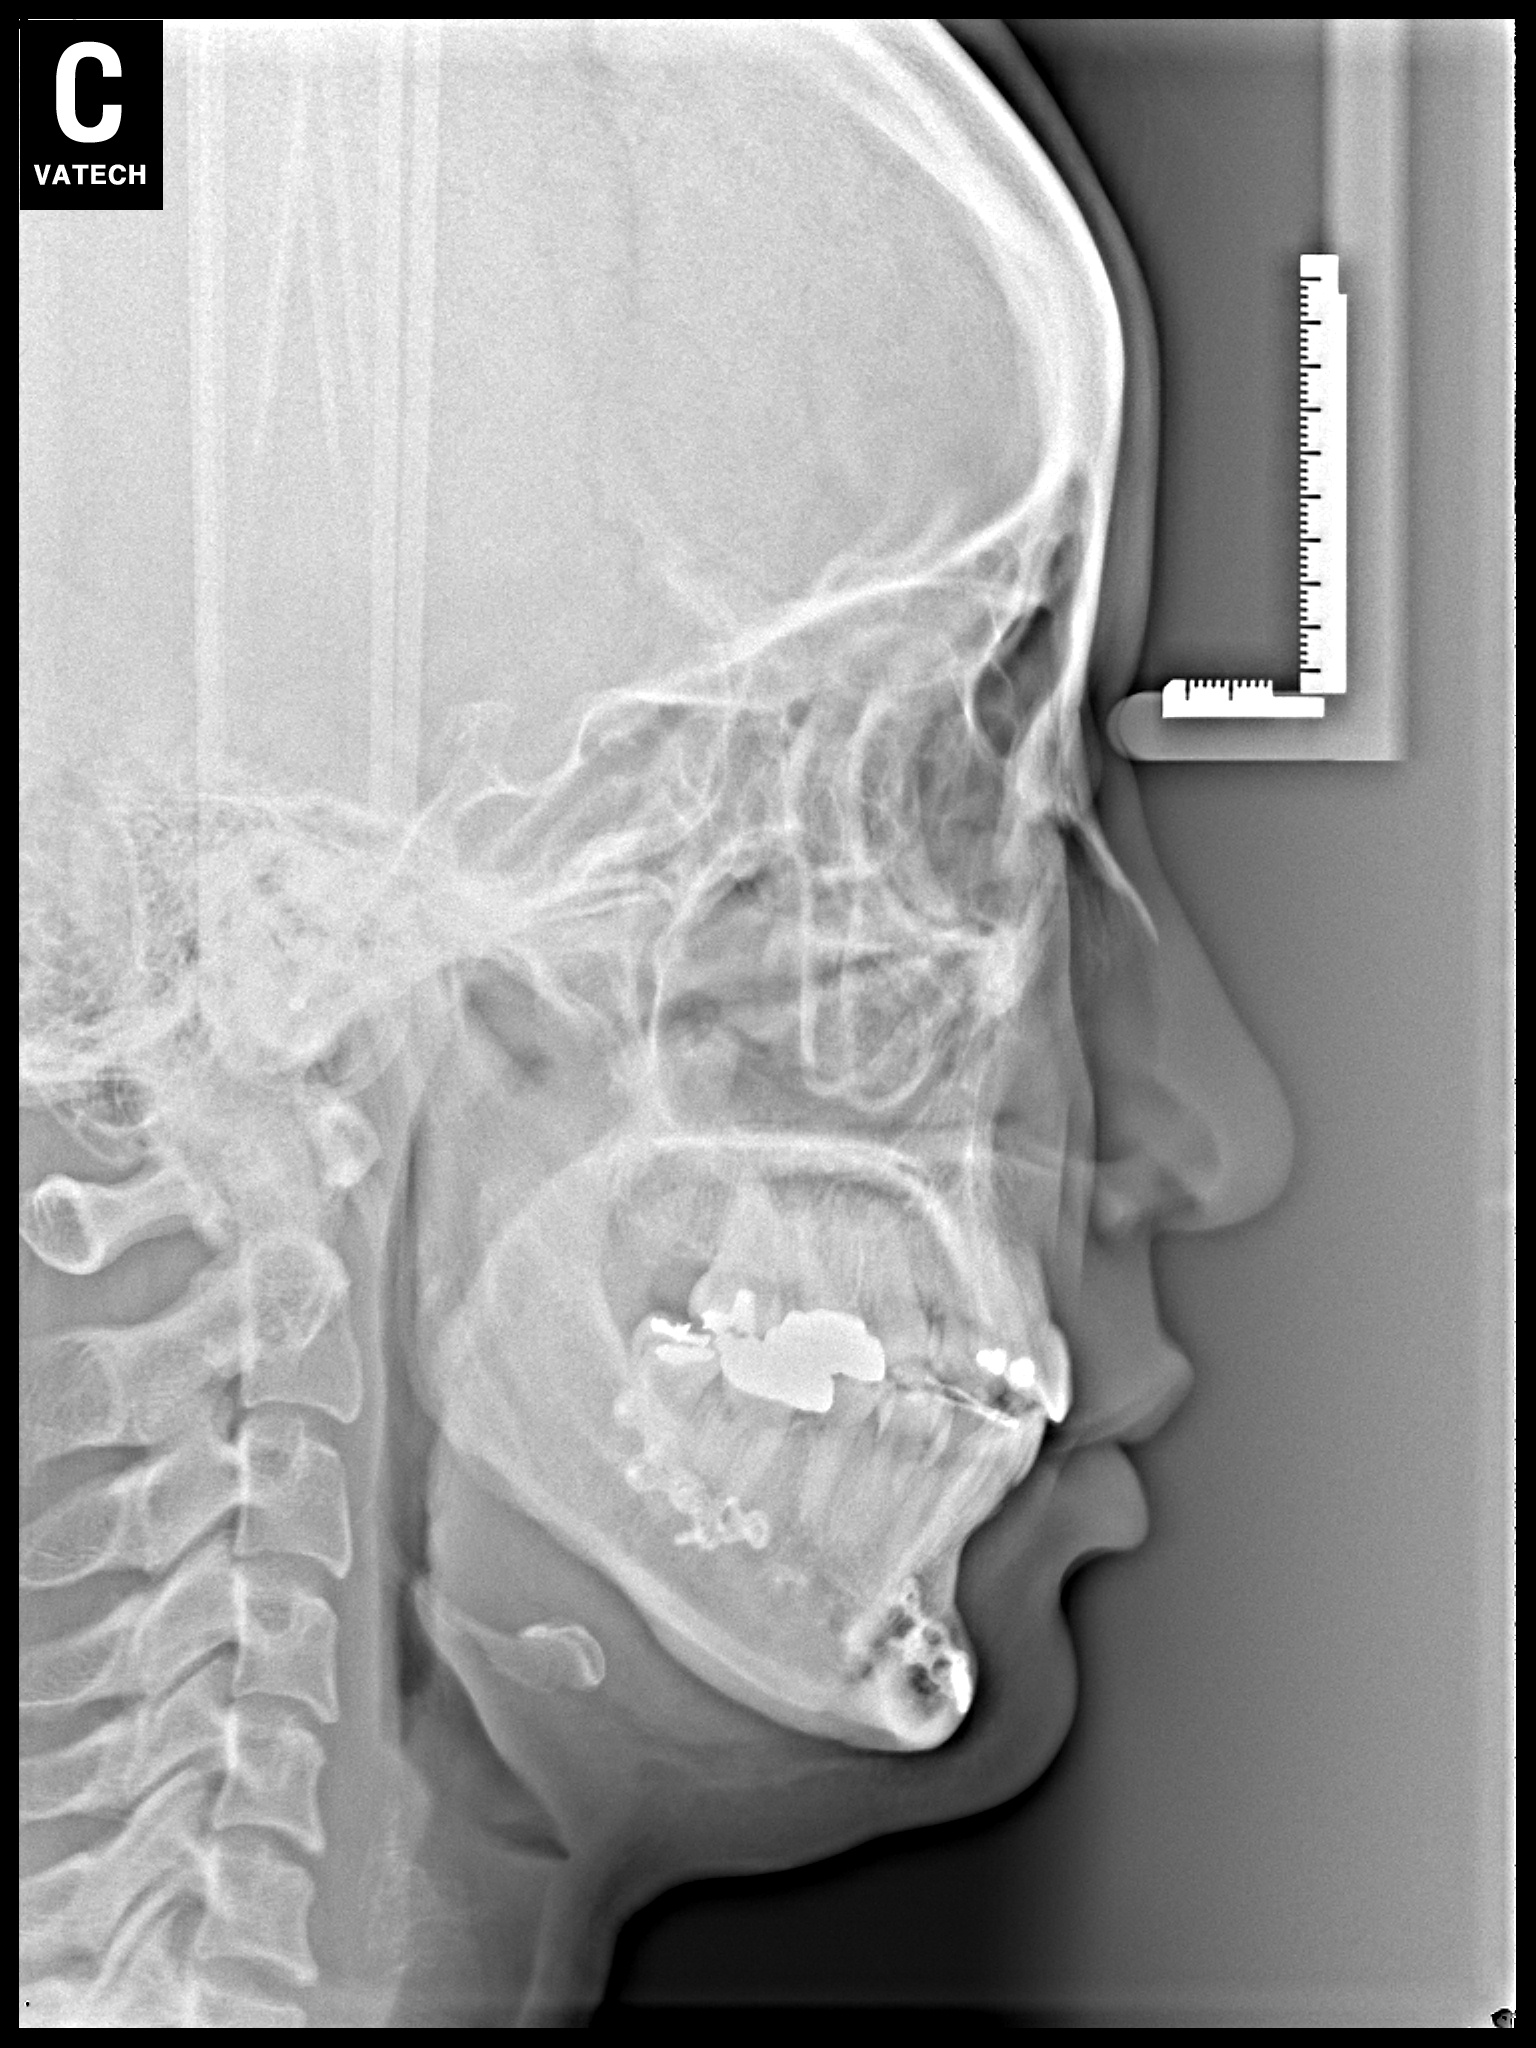

치료 전 사진입니다.